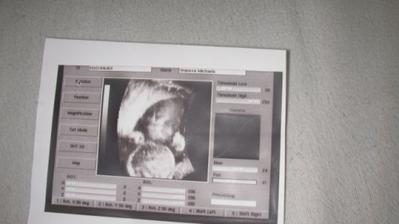

svoj prichod planujem 24.11.2009 a maminka s tatinkom sa na mna veeelmi tesia a taaaaaaaakto velmi moc ma lubia. maminka sa somnou stale rozprava a vravi, ze november je este daleko ale ocko mne a maminke stale hovori, ze to prejde rychlo a uz za chvilku ma budu cuckat a mojkat aj inak ako cez brusinko 🙂 7.8.2009 sme boli na 3D ultrazvuku a sme zdravucky... a pan doktor nam povedal, ze cakame tu najkrajsiu princeznu na svete!!! 7.8.2009 sme boli na 3D ultrazvuku a dozvedeli sme sa, ze cakame tu najkrajsiu princeznicku na svete 🙂)) tatinko sa velmi tesi je to jeho splneny sniiicek 🙂)))